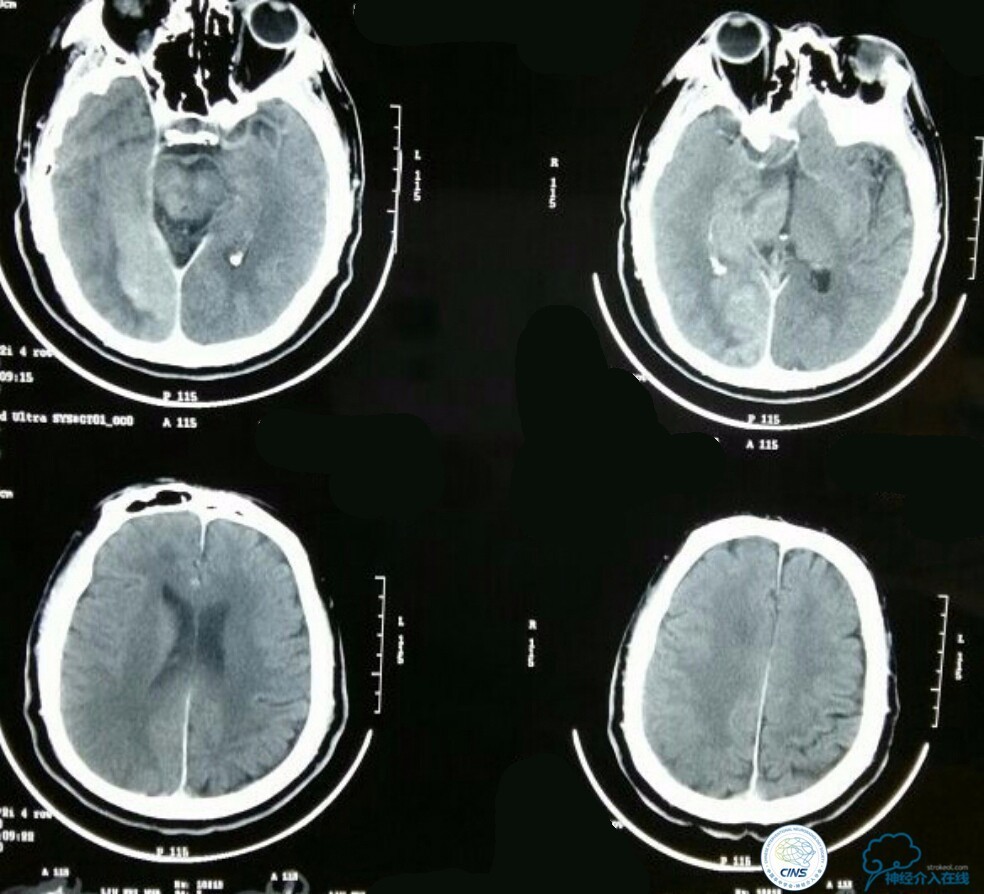

查体:浅昏迷,双侧瞳孔不等大,D右:D左=3.0:1.5mm,对光反射消失,左侧鼻唇沟变浅,左眼闭合不全,左侧肢体肌力0级,左侧病理症(+),其余查体不能配合,内科查体无异常。NIHSS评分:20分,心电图:正常心电图,随机血糖:17mmol/l,头颅CT:未见异常。

急诊MRI+MRA:右侧丘脑及小脑半球多发新鲜梗死病灶,右侧颈内动脉颅内段未见显影,基底动脉尖未见显影!